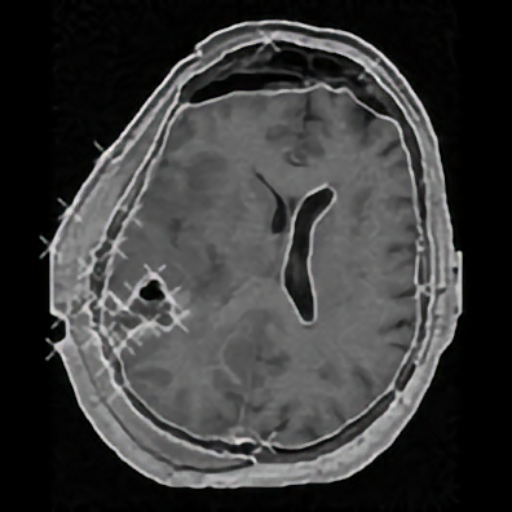

Elastic registration of 2D and 3D multimodal medical images (MR, CT) for diagnosis, surgical planning, and therapy. Spline-based registration approaches using landmarks, intensity information, and landmark localization uncertainties.

Brain shift correction for intraoperative navigation based on elastic registration algorithms.